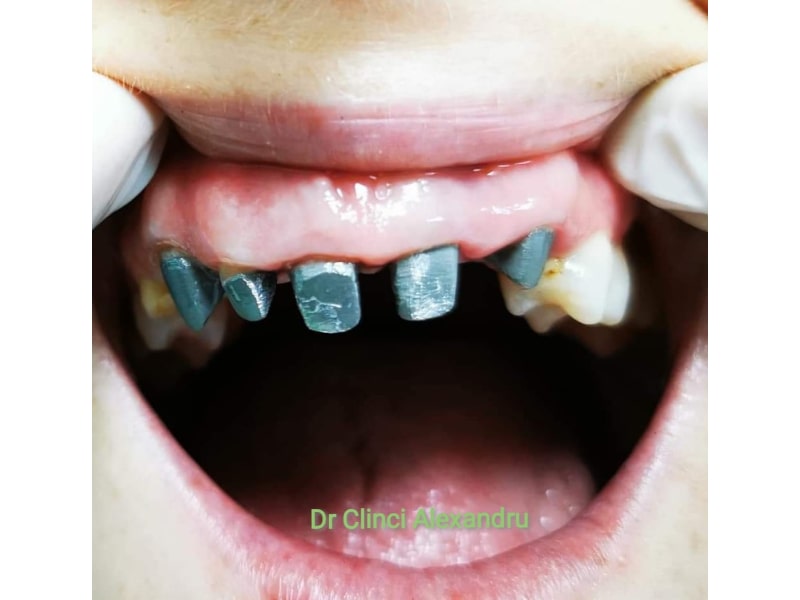

Zirconiu Multilayer